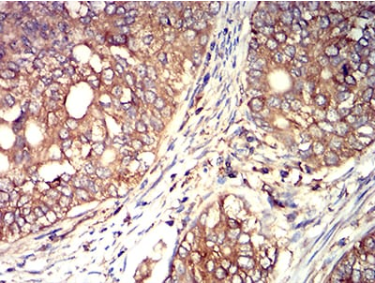

IHC    1/200 - 1/1000